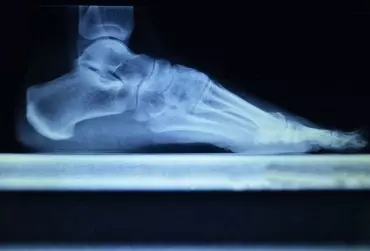

Indywidualne wkładki ortopedyczne

Co zrobić, kiedy pacjent narzeka na bóle stóp oraz kolan, a jednocześnie widoczne jest nierówne ścieranie podeszwy w noszonym przez niego obuwiu? Oprócz prowadzenia terapii manualnej i zalecenia odpowiednich ćwiczeń warto wysłać pacjenta do specjalisty zajmującego się indywidualnym doborem wkładek ortopedycznych.